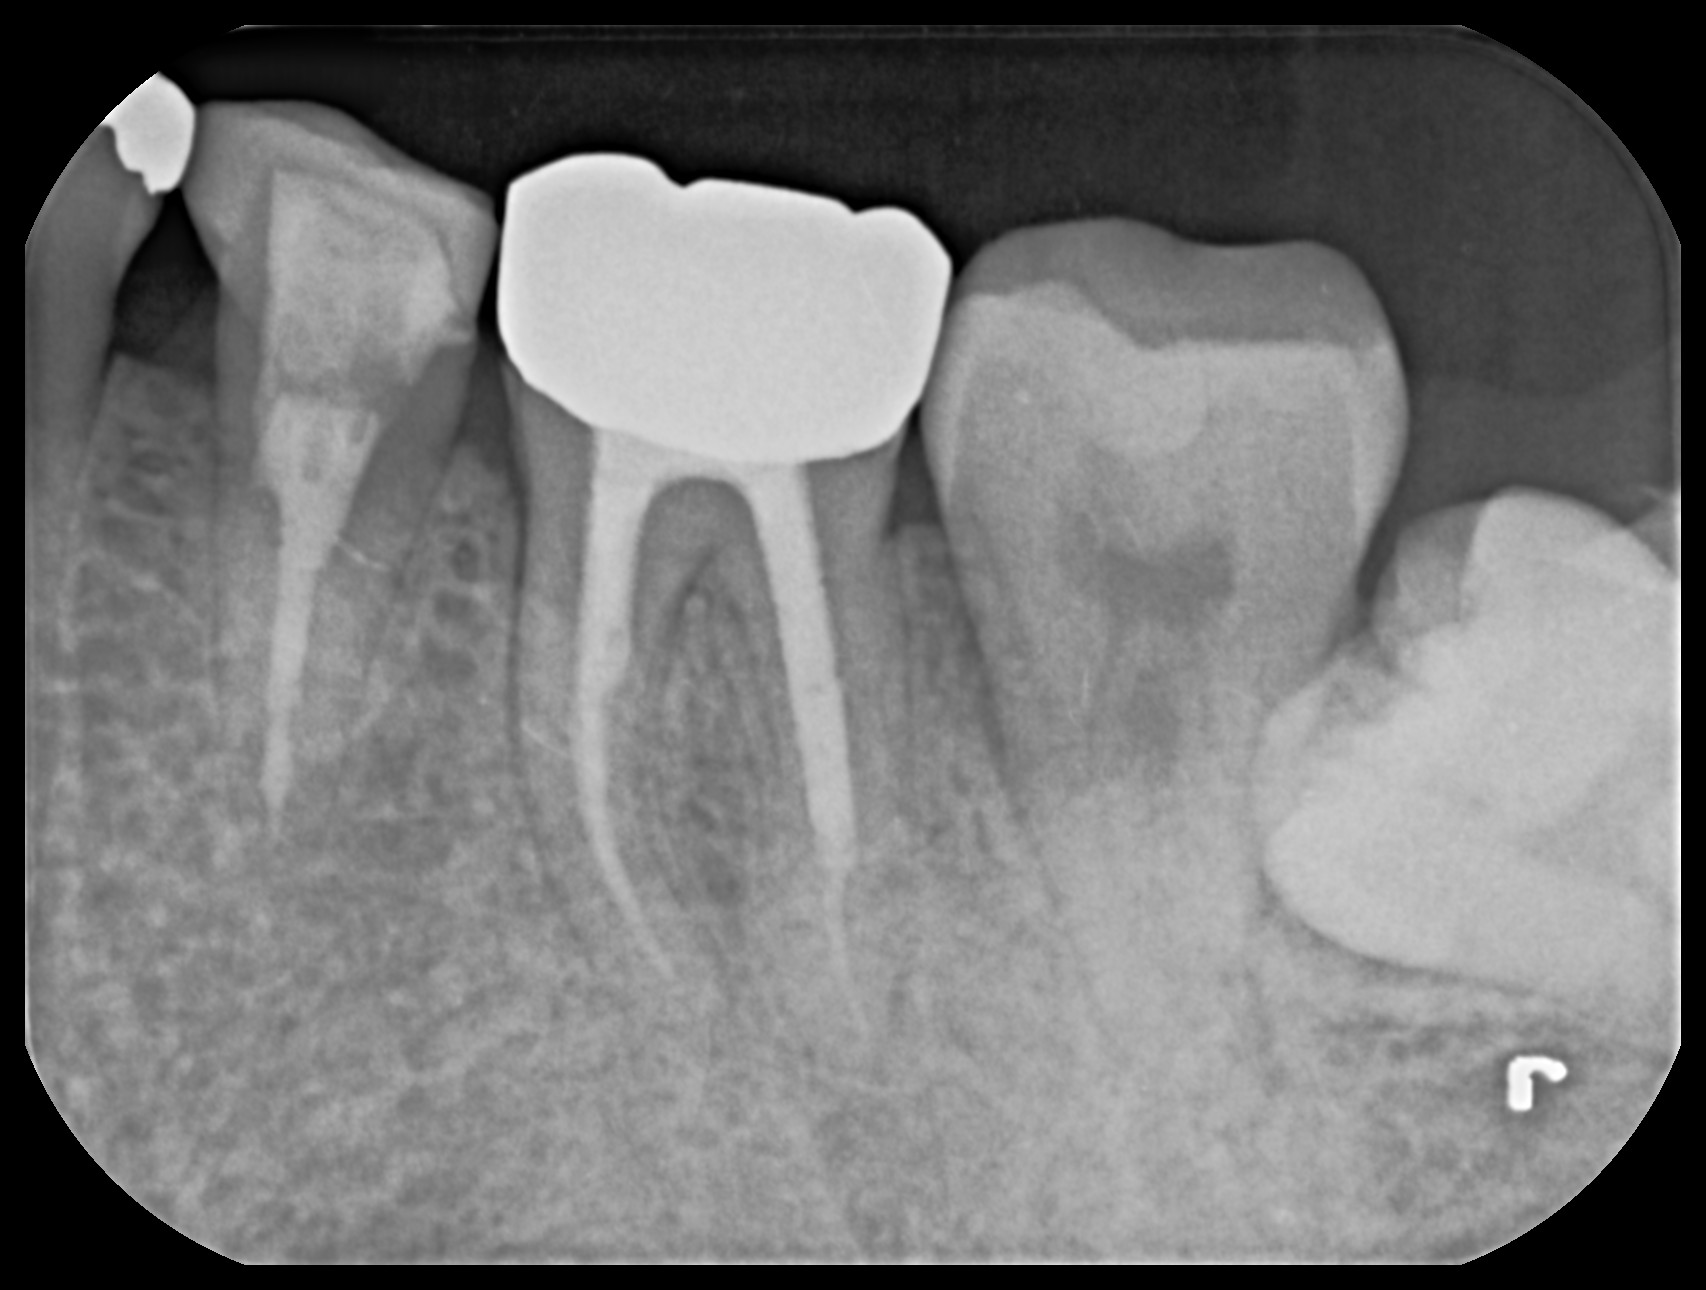

精密根管治療後の経過観察において、噛んだ際の違和感や歯ぐきからの排膿は消失し、症状は安定して推移しています。術後のCT検査では、治療前に認められていた根尖部の大きな透過像(骨吸収像)が縮小し、周囲の骨の回復傾向が確認されました。湾曲の強い根管であったものの、マイクロスコープ下で精密に感染源を除去・封鎖することで、良好な治癒反応が得られています。

治療終了時

歯の残存量が十分に保たれていたことも、治療後の安定した経過につながっており、現在は歯の保存が可能な状態を維持しています。今後も定期的な経過観察を行いながら、長期的な歯の保存を目指していきます。